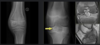

Condroblastoma

Imagem

RX: Lítica, epifisária com esclerose e calcificações no interior

RNM: Cartilagem com calcificações no interior